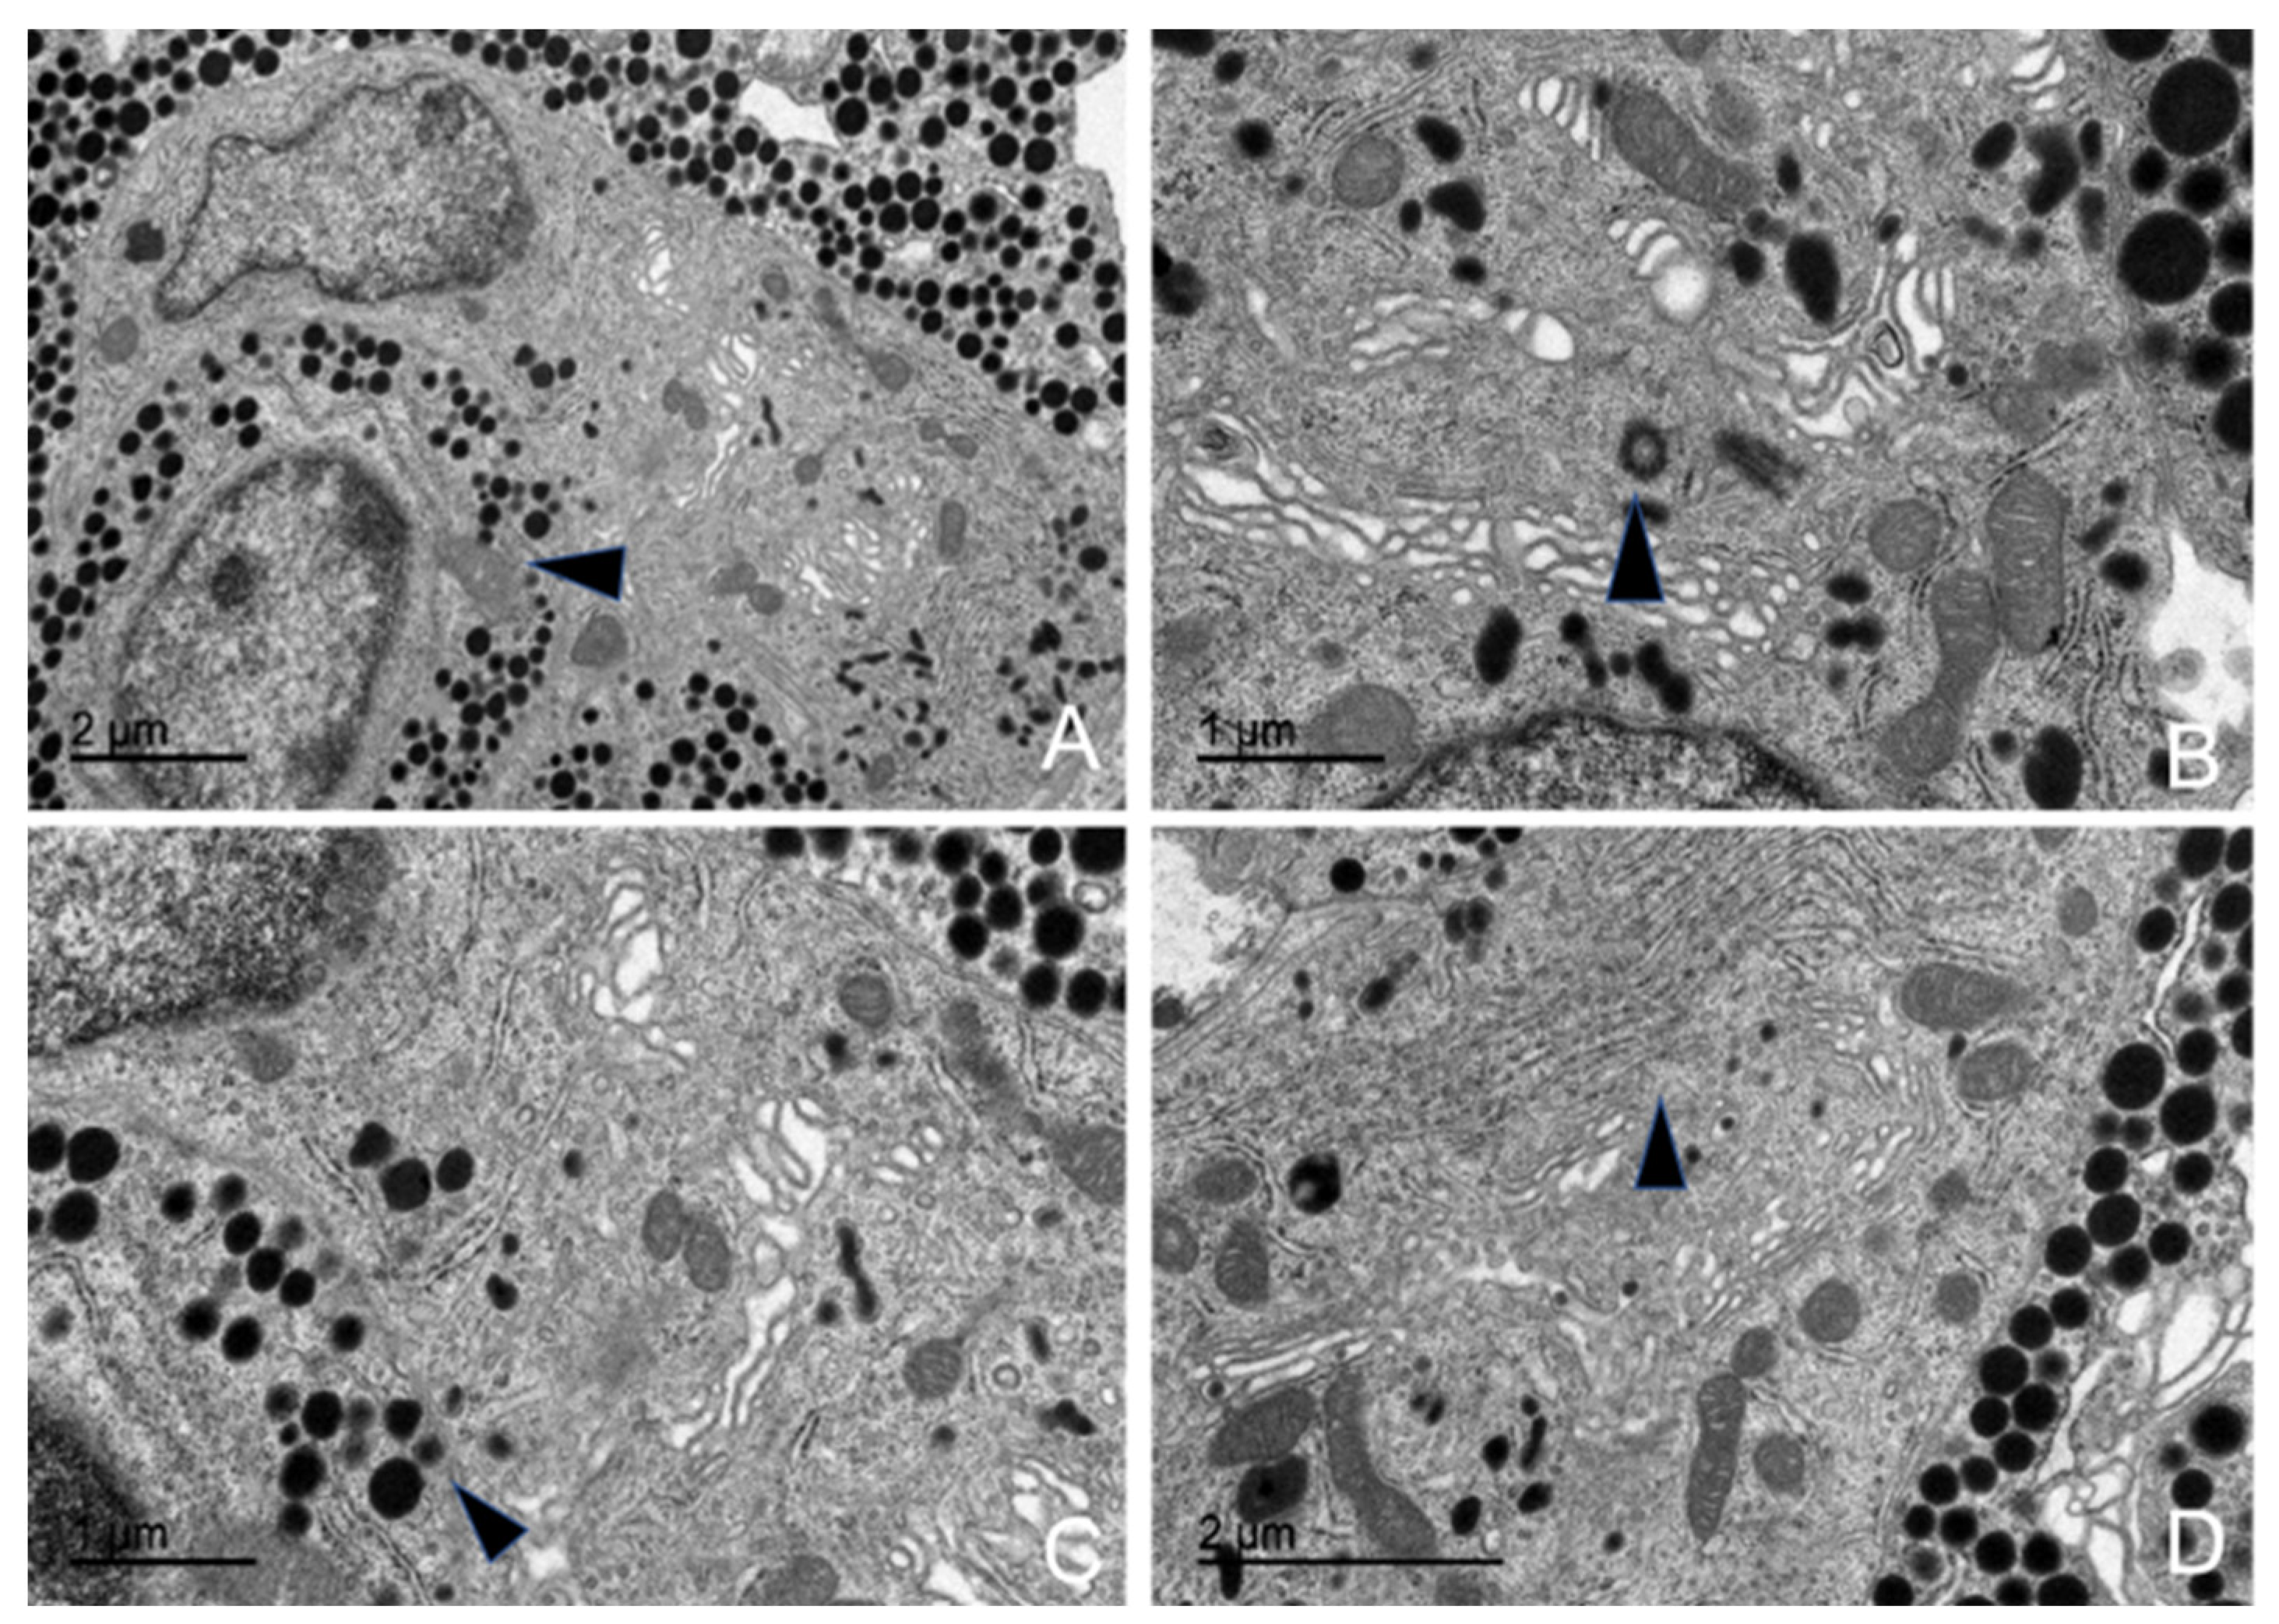

3.5. Ultrastructural Description of the Adenohypophysis Through Transmission Electron Microscopy (TEM)

3.5.1. Corticotrophs (ACTH-Producing Cells)

3.5.2. Lactotrophs (LTH-Producing Cells)

3.5.3. Somatotrophs (GH-Producing Cells)

3.5.4. Gonadotrophs (GnRH -Producing Cells)

3.5.5. Thyrotrophs (TSH-Producing Cells)

3.5.6. Melanotrophs (MSH-Producing Cells)

3.5.7. Follicular Cells

3.5.8. Capsular Cells